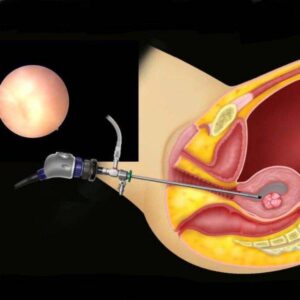

Υστεροσκόπηση

Η υστεροσκόπηση (hysteroscopy) είναι μια ιατρική διαδικασία που χρησιμοποιεί ένα λεπτό, φωτιζόμενο ένθετο που ονομάζεται υστερόσκοπο, για να εξετάσει το εσωτερικό της μήτρας και τον τραχήλο. Σε ορισμένες περιπτώσεις, μπορεί να γίνει και θεραπευτικός χειρισμός κατά τη διάρκεια της υστεροσκόπησης.

Συνήθως, η υστεροσκόπηση πραγματοποιείται για τους εξής λόγους:

- Διάγνωση Προβλημάτων: Η υστεροσκόπηση μπορεί να χρησιμοποιηθεί για τον εντοπισμό προβλημάτων στη μήτρα, όπως πολυποδες, κόλπικοι δακτύλιοι, ή ανωμαλίες στον τραχήλο.

- Αντιμετώπιση Προβλημάτων: Κατά τη διάρκεια της υστεροσκόπησης, μπορεί να πραγματοποιηθεί θεραπευτικός χειρισμός για την αφαίρεση πολύποδων, πολικών κυστών, ή άλλων παθήσεων.

- Εφαρμογή Παρακολούθησης: Η υστεροσκόπηση μπορεί να χρησιμοποιηθεί για τον έλεγχο της αποτελεσματικότητας θεραπειών, όπως η αφαίρεση πολυπόδων, και για παρακολούθηση της προόδου μετά από χειρουργική επέμβαση.

Η διαδικασία γίνεται συνήθως σε έναν εξοπλισμένο κλινικό χώρο ή στο χειρουργείο. Σε ορισμένες περιπτώσεις, μπορεί να χρησιμοποιηθεί τοπικό ή γενικό αναισθητικό κατά τη διάρκεια της διαδικασίας. Η υστεροσκόπηση αποτελεί ένα σημαντικό εργαλείο για τον γυναικολόγο για τη διάγνωση και τη θεραπεία προβλημάτων που επηρεάζουν τη μήτρα και τον τραχήλο.